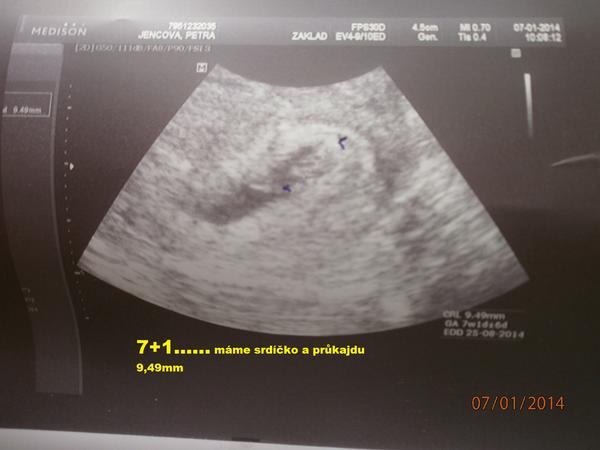

@japro tak koukej bojovat...mě bude 35 ted 24.1.....zítra jdu na ko 7+1...jsem celá nervní co tam bude nebo nebude :-/

@petrusejenc jj budu se snažit 🙂díky ...... držím mooooc palečky a těším se na foto 🙂 at je vš v pořádku .-)